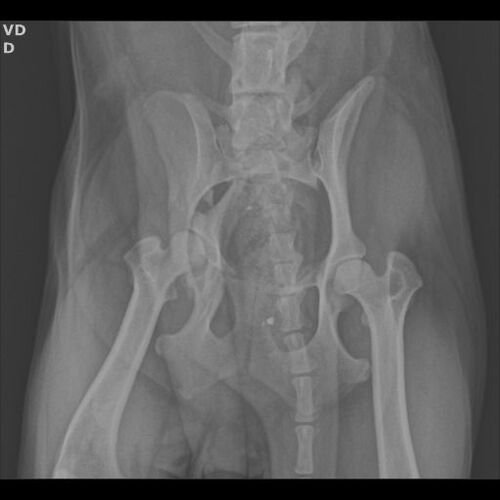

No dia 24, uma cadelinha foi atropelada na frente da nossa casa. Ao ver a situação, não conseguimos ignorar e imediatamente prestamos socorro, levando-a ao veterinário.

Desde então, ela está internada, recebendo cuidados, exames e medicação. Infelizmente, devido à gravidade do atropelamento, ela precisará passar por uma cirurgia ortopédica de quadril urgente para ter chance de recuperação e voltar a andar e viver sem dor.